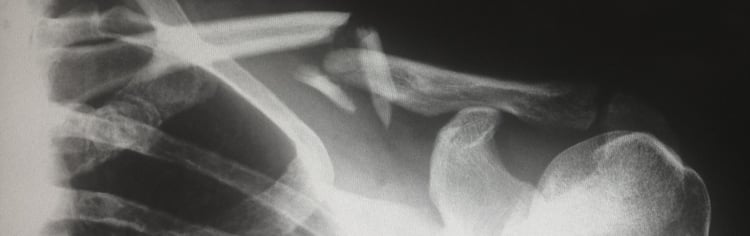

Un indépendant est reconnu en incapacité de travail en cas de lésion physique ou psychique (comme par exemple une maladie, une opération lourde ou des problèmes psychologiques) l’empêchant d’exercer son activité indépendante. Une distinction est opérée entre l’incapacité de travail primaire d’une part et l’invalidité d’autre part.